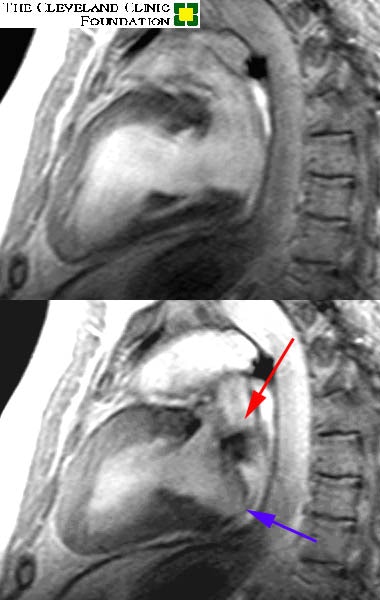

Image set #1 is a two chamber long axis view through the left ventricle and left atrium. Image set #2 is a four chamber view. The upper images are in diastole, while the lower are in systole. The red arrow demonstrates the turbulent jet of regurgitant blood flowing back into the left atrium. Regurgitation has occurred as a result of the 'prolapsing' posterior leaflet of the mitral valve noted by the blue arrow.

Image 1: